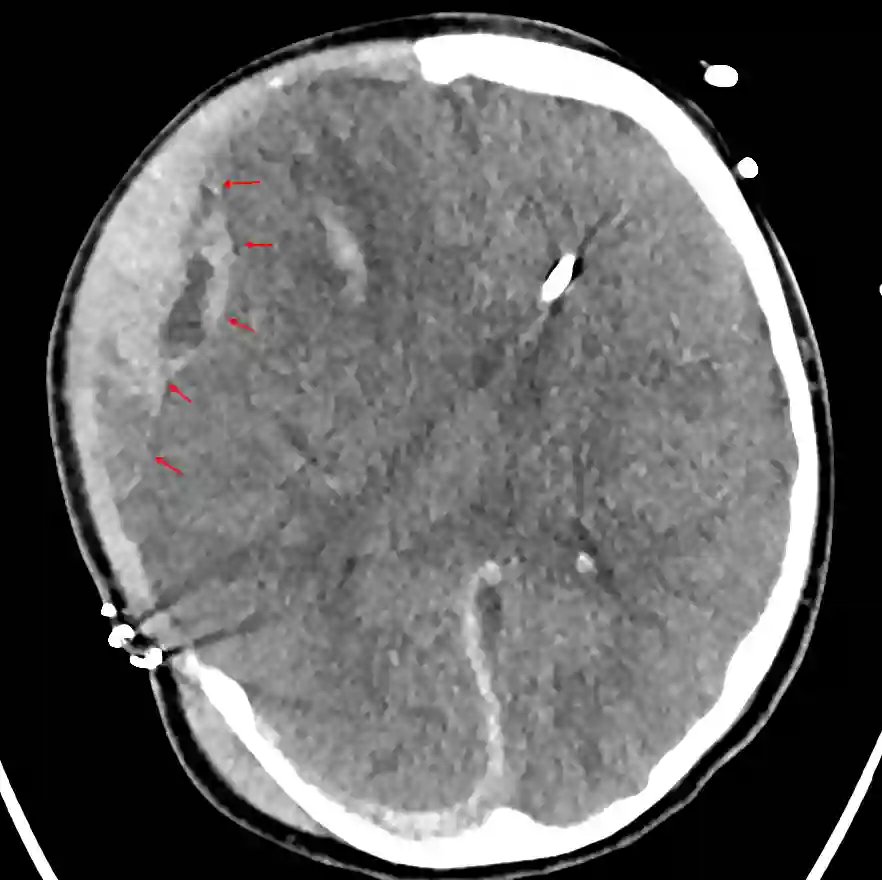

Extra-axiale Nachblutung nach Hemikraniektomie

Darstellung einer extra-axialen Nachblutung auf der rechten Seite bei einem Patienten nach durchgeführter Hemikraniektomie.